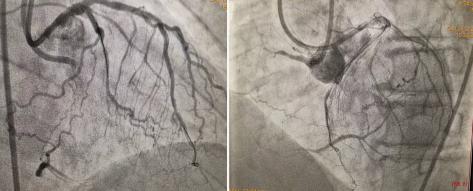

正向135cm1.8F微導(dǎo)管支持下再次嘗試GAIA3、PILOT200仍失敗,立即逆向送入150cm1.8F微導(dǎo)管至前降支遠(yuǎn)端,SION導(dǎo)絲塑小彎進(jìn)入預(yù)先選擇的間膈支,且順利通過(guò)間隔支至右冠閉塞段遠(yuǎn)端,微導(dǎo)管亦順利跟進(jìn)至右冠閉塞段內(nèi)。此時(shí),逆向?qū)Ыz如何進(jìn)入正向?qū)Ч軆?nèi)成為手術(shù)難題,既往多數(shù)病人皆因此而手術(shù)失敗。此時(shí)手術(shù)團(tuán)隊(duì)利用AGT技術(shù),正向指引導(dǎo)管內(nèi)送入Guidezilla延長(zhǎng)導(dǎo)管“出門迎客”,逆向微導(dǎo)管順利進(jìn)入正向延長(zhǎng)導(dǎo)管,此過(guò)程歷時(shí)約3分鐘,至此預(yù)示手術(shù)基本成功,右冠成功開(kāi)通。整個(gè)手術(shù)耗時(shí)70分鐘,造影劑量150ml。

圖2  AGT技術(shù)—正向Guidezilla延長(zhǎng)導(dǎo)管成功迎接逆向微導(dǎo)管